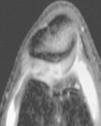

Figura 5 RM. Imagen potenciada en T1. Cuerpos libres alrededor de los ligamentos cruzados y en otras localizaciones intraarticulares.

Figura 6 Artroscopia. Cuerpos libres alrededor de los ligamentos cruzados y en otras localizaciones intraarticulares.

Figura 7 Artroscopia. Cuerpos libres alrededor del ligamento cruzado íntegro.

Figura 8 Artroscopia. Cuerpos libres alrededor del ligamento cruzado íntegro.